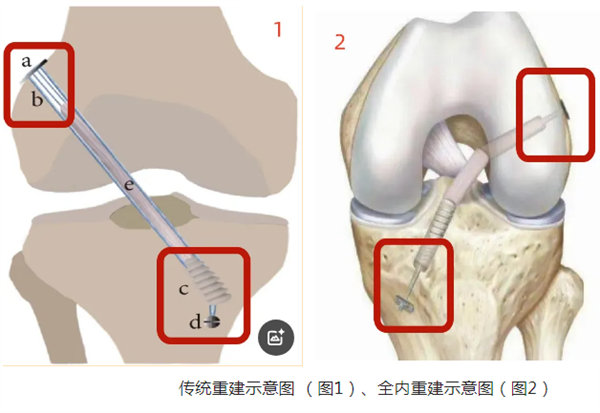

全內重建技術是指采用可翻轉鉆翼倒打鉆制作半長股骨、脛骨隧道,將編織好兩端已掛上可調節袢鋼板的移植肌腱從膝關節鏡的前內入路引入至股骨和脛骨隧道,最后兩側收緊可調節袢鋼板,從而將肌腱移植物分別固定于脛骨、股骨表面。

與傳統的關節鏡下前交叉韌帶重建有什么區別?

傳統的關節鏡下ACL重建方式是全長脛骨隧道ACL重建,其存在移植物要求高(長度和直徑)、骨質損傷大、內固定不牢固等技術缺陷;ACL全內重建技術兩個主要特征是采用雙側半長骨隧道和襻鈦板懸吊固定,具有降低手術創傷、節省肌腱、保留骨量和增強固定強度的優勢,被認為是目前最符合國人解剖特點和重建需求的ACL重建術式之一。

傳統重建示意圖 (圖1)、全內重建示意圖(圖2)